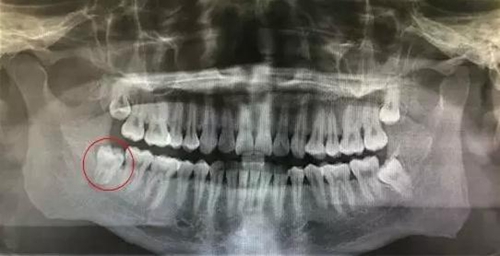

患者,王xx、男,30歲。主訴:右側(cè)下頜后牙牙齦反復(fù)腫痛,要求拔除。??茩z查:48近中頰尖已萌出,牙齦覆蓋牙冠約3/4,遠(yuǎn)中有盲袋,牙齦色澤正常,開(kāi)口度正常。全景片影像檢查:48垂直位,雙根環(huán)抱,遠(yuǎn)中有牙囊影。診斷:48中位垂直阻生。治療計(jì)劃:建議拔除 48?;颊咄獍纬?,簽術(shù)前知情同意書。

圖2.局部放大的影像學(xué)檢查:48雙根環(huán)抱型,遠(yuǎn)中有牙囊影。